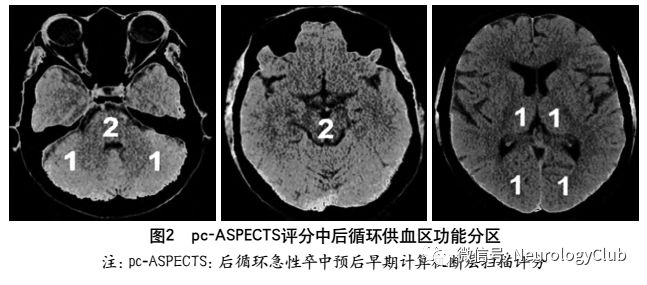

为评估后循环梗死患者早期梗死情况,PUETZ等建立了评估后循环的AIS预后早期CT评分(posterior circulation Acute Stroke Prognosis Early CT score,pc-ASPECTS)。pc-ASPECTS总分也是10分:双侧丘脑和小脑各1分,双侧大脑后动脉供血区各1分,中脑和脑桥为2分(图2)